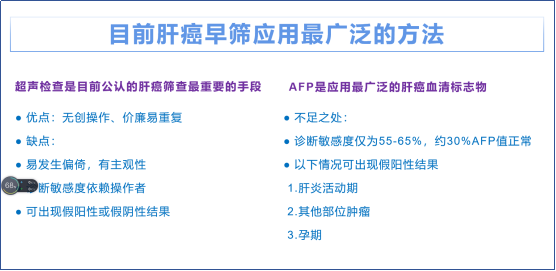

医生介绍道,早期肝癌大多没有明显症状,不易察觉。hvT帝国网站管理系统

少数患者会出现上腹部闷胀、腹痛、乏力、食欲下降等慢性肝病症状。晚期患者可表现为肝区疼痛、食欲减退、消瘦、乏力、发热、黄疸、上消化道出血等。hvT帝国网站管理系统

专家表示,希望大家在日常生活中多多关注自己的身体,出现异样症状后千万不要一拖再拖,导致错过治疗良机。